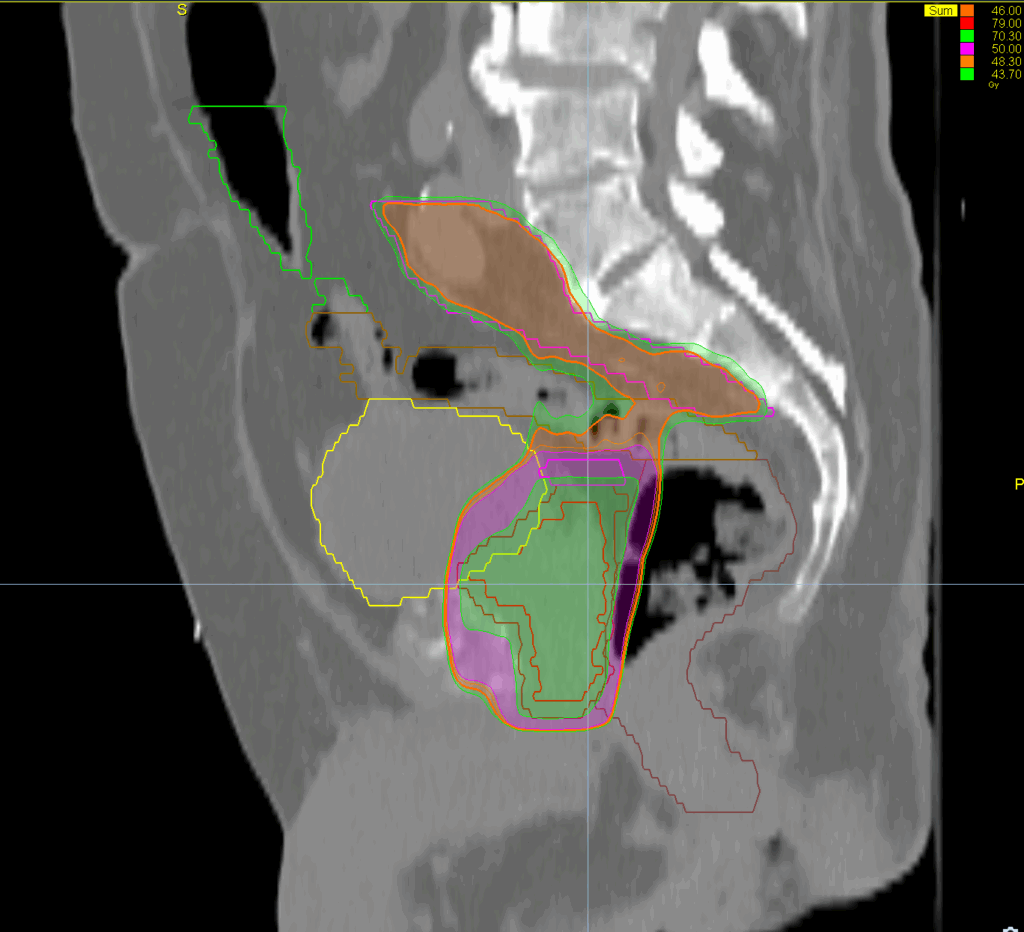

Treatment Plan Images

ClearRT® Images

Treatment Delivery Information

Imaging Information

ClearRT®

Protocol

Pelvis-normal-FOV50cm

Scan Length

9 cm

KVCT Imaging Time

18 sec

Beam on Time

4.6 min and 2.15 min